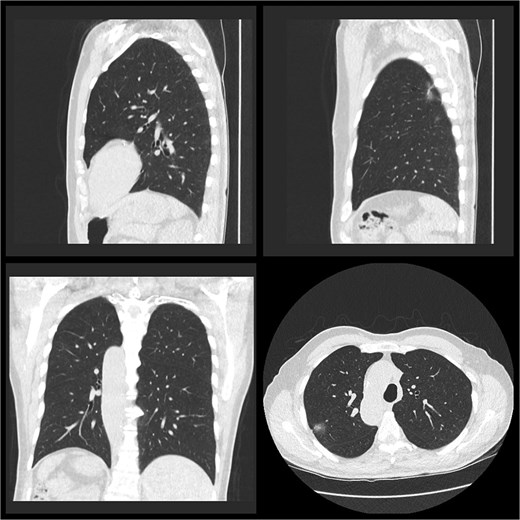

A 73-year-old gentleman was referred to our cardiothoracic department with a tumour of his right upper and right lower lobe diagnosed on computed tomography (CT), as seen in Fig. 1. He initially presented to his general practitioner (GP) with fatigue and weight loss. His background included ex-smoker with five pack-year history having quit 40 years prior, mild chronic obstructive pulmonary disease type 2 diabetes mellitus, dyslipidaemia, peptic ulcer disease, gastro-oesophageal reflux disease, diverticulosis, and colonic polyps. The patient has been known to have SIT since his early adulthood, an incidental finding on a chest X-ray.

A low-dose CT chest (Fig. 1) showed a nodule in the right upper lobe of 20 × 20 mm in diameter with a central solid component 7 × 4 mm and an 8-mm diameter ground glass opacity with a central solid dot in the right lower lobe. No lymphadenopathy was detected.